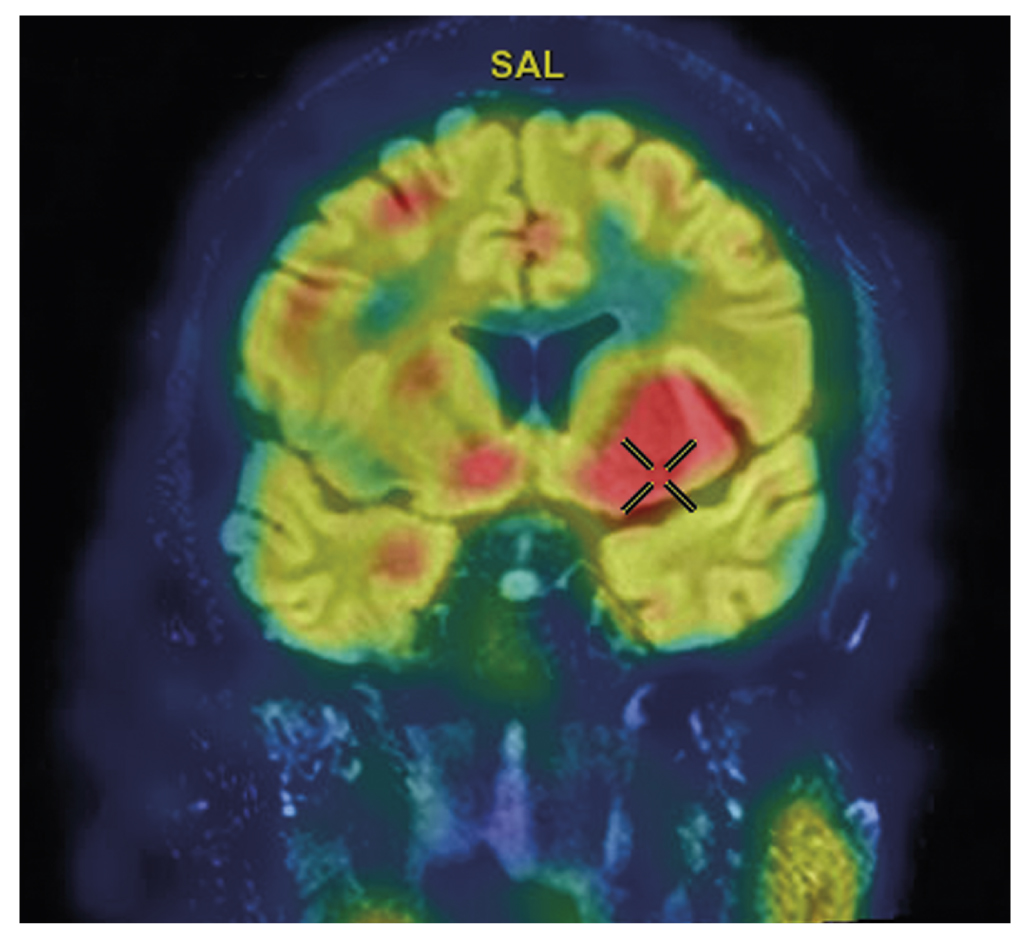

Figure 3 shows SISCOM images of a patient’s brain with complex partial seizures, indicating increased perfusion in the anterior pole of the right temporal lobe, primarily in the medial region [64].

Fig. 3. A fused SISCOM image (SPECT of the brain performed during a complex partial seizure combined with MRI of the brain) demonstrating hyperperfusion in the basal ganglia and insula of the left hemisphere (courtesy of FSBI «FCMN» FMBA of Russia).